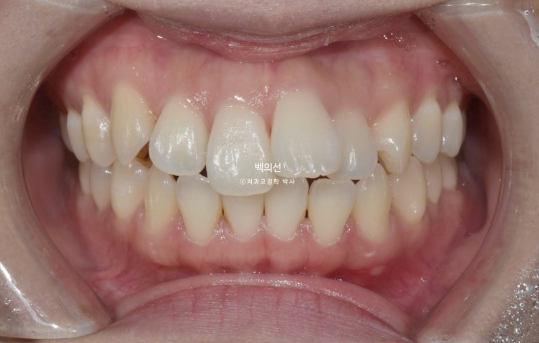

23년 1월 교정을 위해 내원한 30대 환자분입니다.

고치고 싶은 것은 돌출입이였고 장치는 인비절라인 선택하셨습니다.

앞니 덧니가 보입니다.

중심선이 약 2mm 어긋나 있습니다.

앞니 뻗침은 심한 편 입니다.